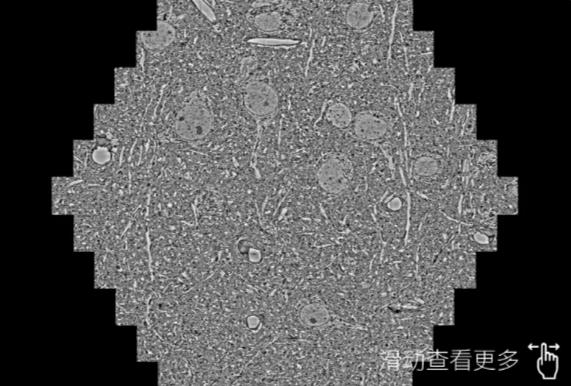

鼠脑切片。左图使用常州蔡司常州扫描电镜MultiSEM706对165μmx143pm面积区域成像,耗时仅需1.5秒。右图为鼠脑切片中30μm区域放大效果。样品由芝加哥大学B.Kasthuri提供。

使用蔡司高速常州扫描电镜MultiSEM对1mm²人脑皮层组织进行高分辨成像,并对其中的各种细胞结构进行三维重构分析。左图展示了2x3mm²组织平面中锥体神经元的三维重构效果。右图显示了局部体积神经元三维重构。图像由哈佛大学chtman实验室提供,渲染图由D. Berger 制作。